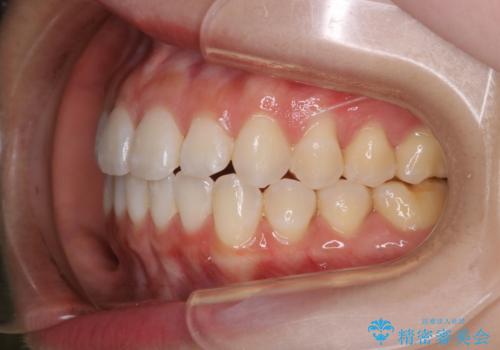

前歯で噛めない:オープンバイト(開咬)を非抜歯インビザラインで治療

- 上下の歯が噛んでいないことを気にしてご相談にいらした方です。

舌癖も認められたため、舌のトレーニングも併せて行い、矯正治療の効率化を図ると同時に後戻りのリスクを最小限に抑えるようにしました。

オープンバイトの方への治療は、通常抜歯を行いワイヤーによる矯正治療を行うことが多いですが、今回はインビザラインの特性を生かし、非抜歯にて綺麗な歯並びを作ることが出来ました。